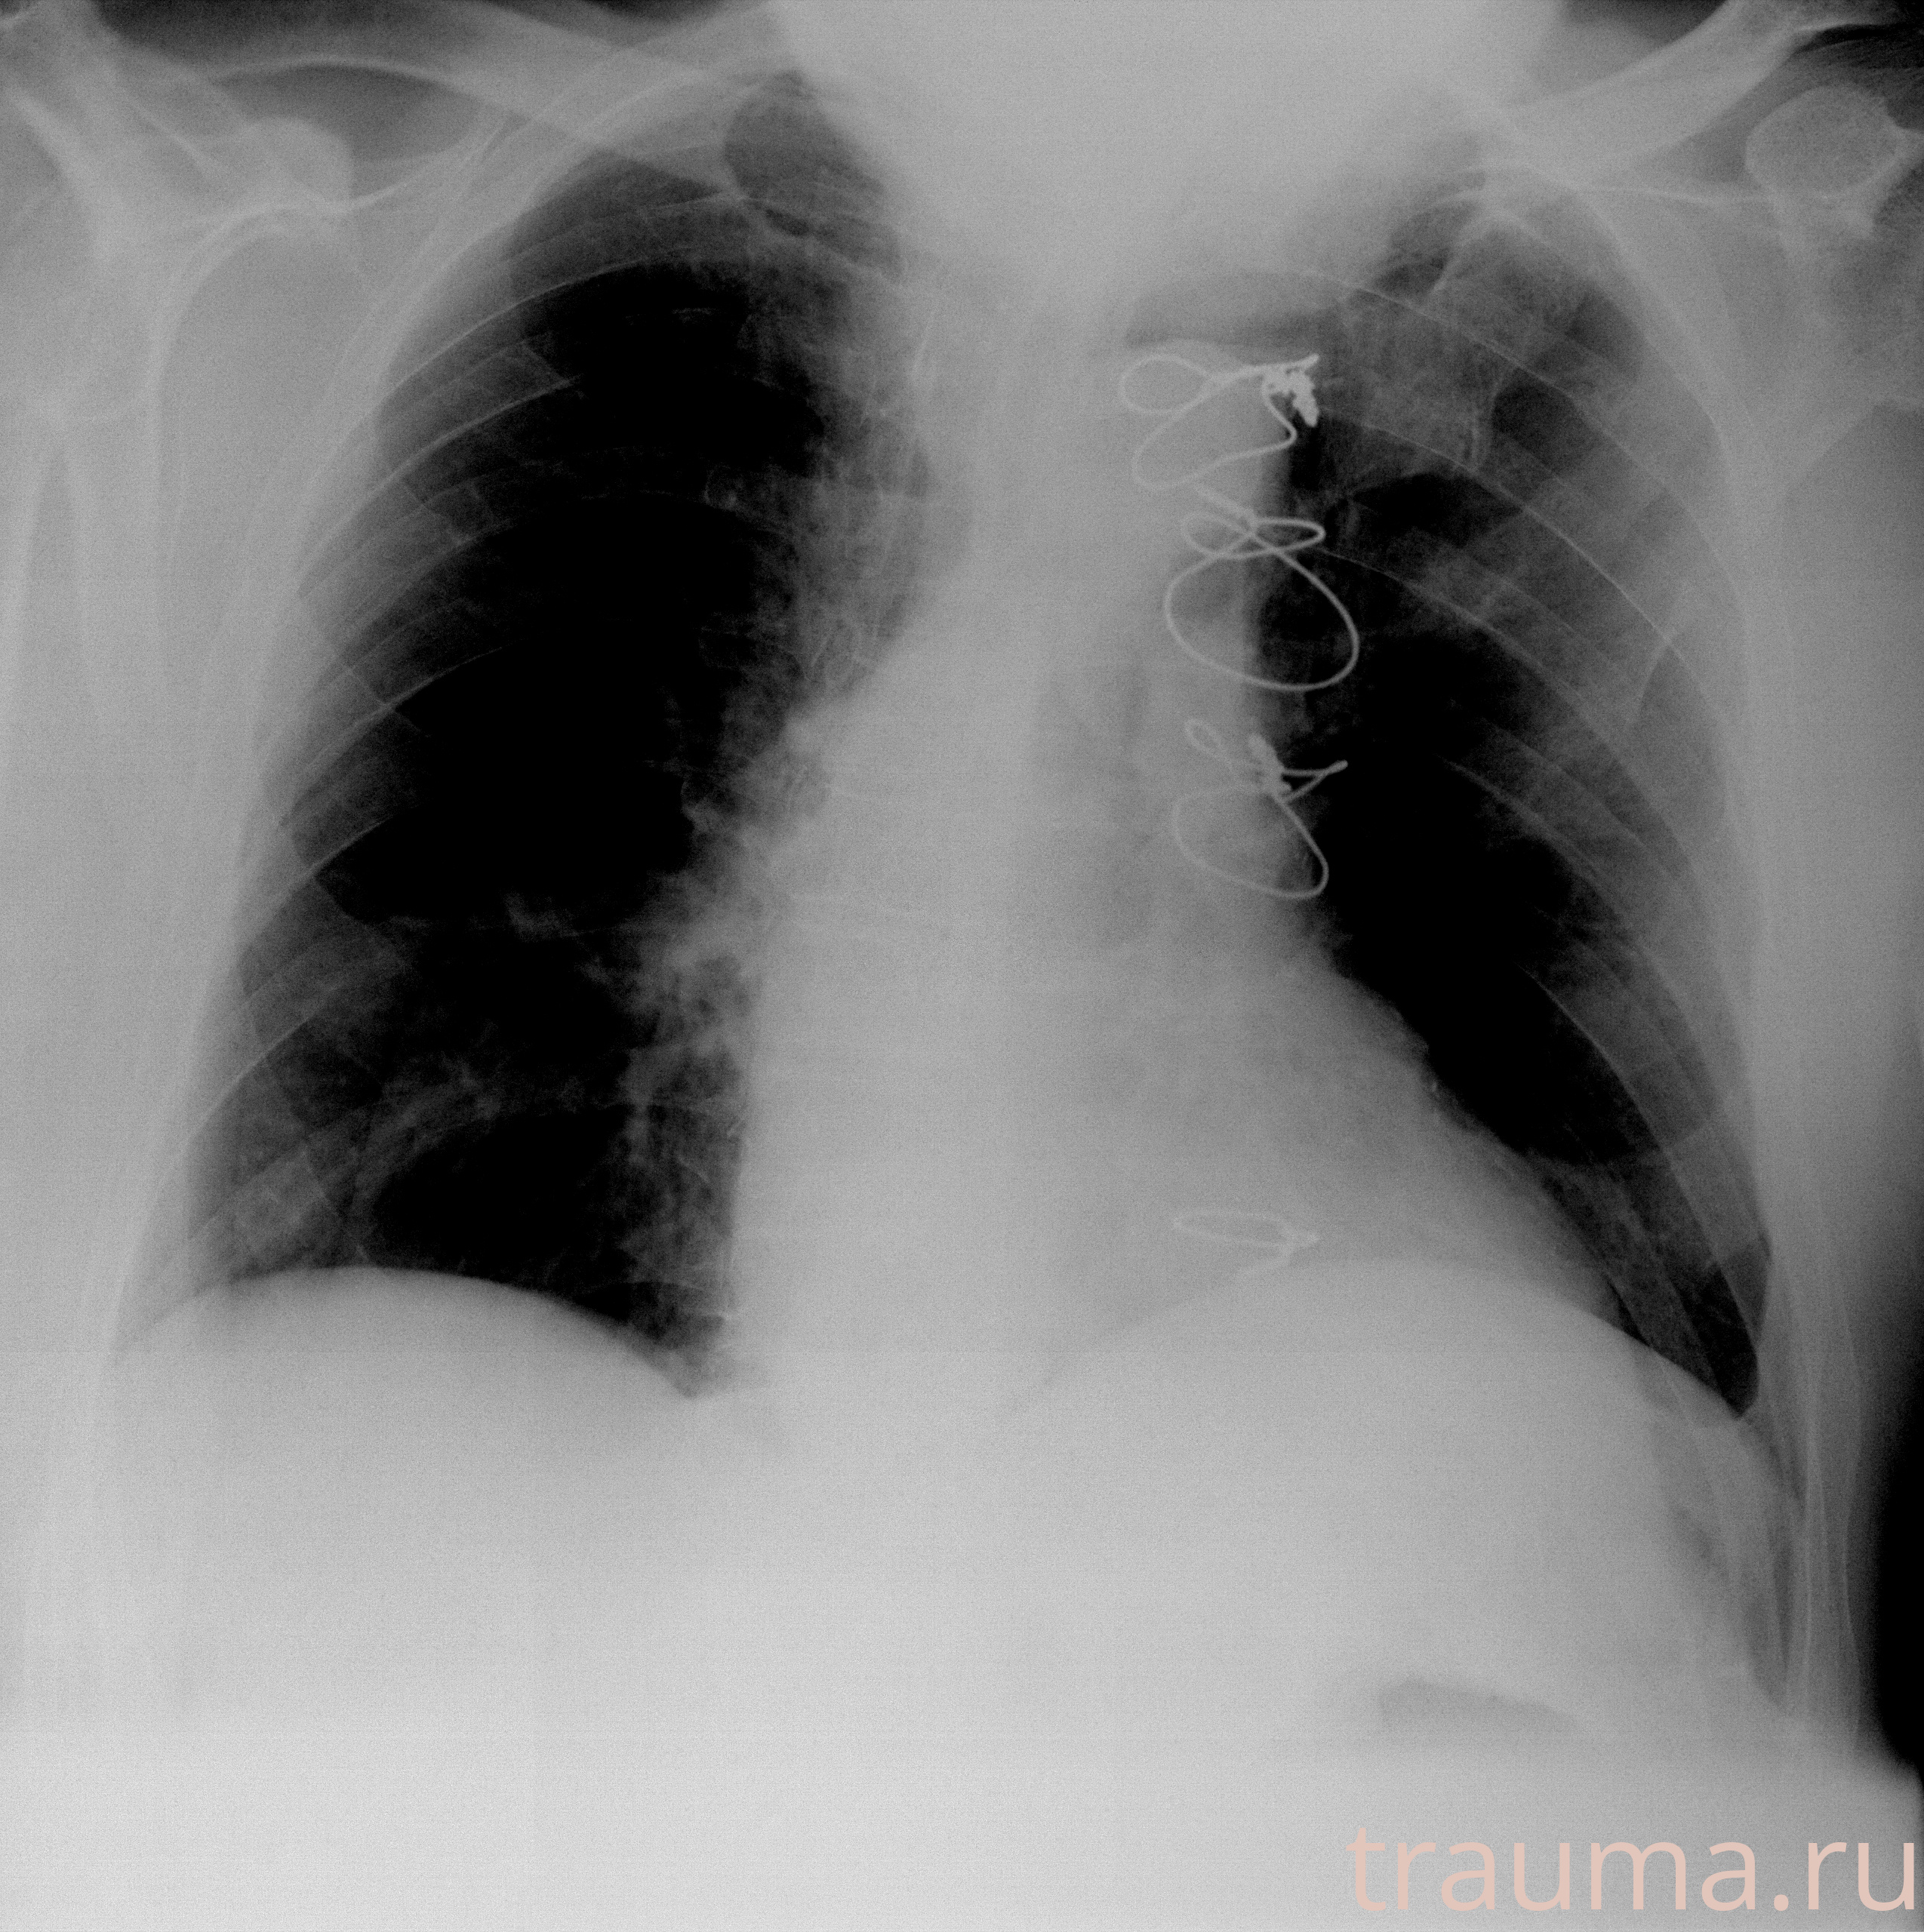

Рентген на дому: по вашему адресу приезжает врач-рентгенолог, травматолог-ортопед с мобильным рентгеновским аппаратом, проводит диагностику травмы или заболевания, делает необходимые рентгенограммы, дает рекомендации по дальнейшему лечению. Получить качественные снимки в домашних условиях возможно благодаря уникальной методике, разработанной МосРентген Центром для института  Склифосовского

при переломе шейки бедра и пневмонии от компании МосРентген Центр - партнера Института имени Склифосовского